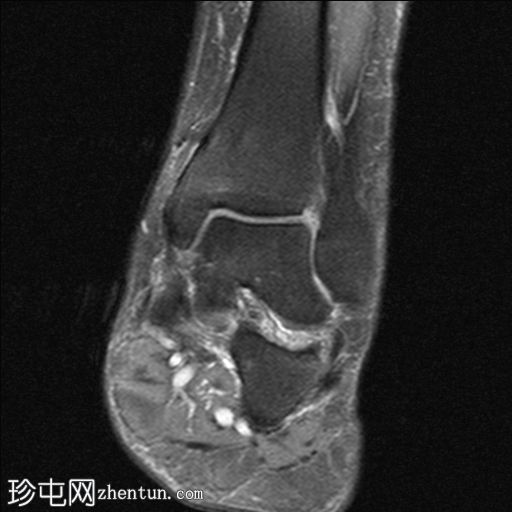

矢状面

T1

跟腱远端1/3信号强度增高且增厚,提示跟腱病变。

跟腱远端部分撕裂

跟腱前滑囊积液导致扩张,提示滑囊炎。